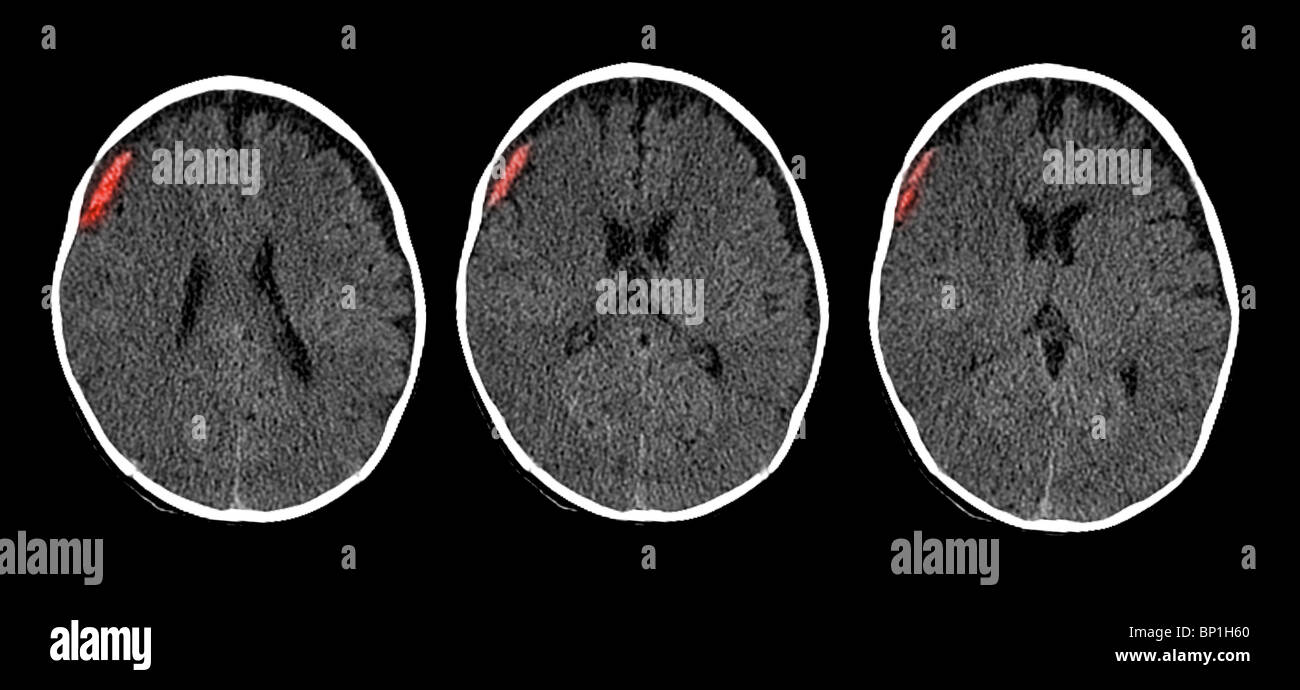

8 Traumi Cranici Casi Diversi Studiati In Tc A Ematoma Epidurale Download Scientific Diagram